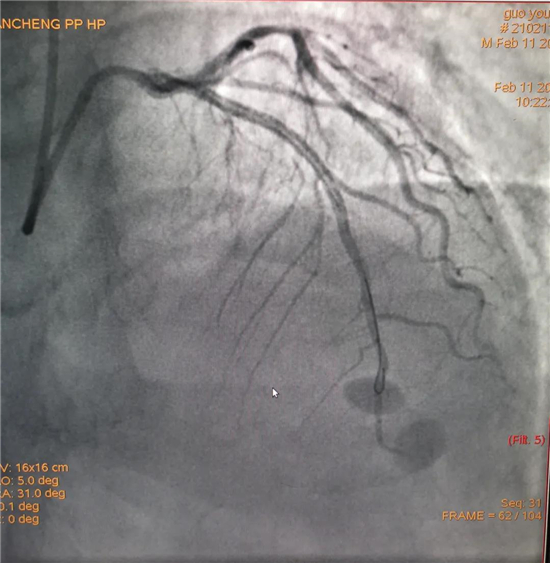

除夕,郭先生無(wú)明顯誘因突發(fā)胸痛,120急救人員到達(dá)現(xiàn)場(chǎng),心電圖顯示:竇性心律完全性束支傳導(dǎo)阻滯。信息立刻發(fā)送到胸痛中心介入微信群中,心內(nèi)科值班醫(yī)生初步診斷為急性廣泛前壁心肌梗死,必須盡快進(jìn)行急診支架治療,開(kāi)通血管。值班醫(yī)生電話指導(dǎo)院前治療,并立即啟動(dòng)胸痛綠色通道,24小時(shí)備班的介入治療團(tuán)隊(duì)立即到位,9:30患者被送到導(dǎo)管室行冠脈介入診療,9:40急診PCI手術(shù)隨之開(kāi)始,冠脈造影檢查提示左前降支閉塞,植入支架,堵塞的血管被順利打通,患者癥狀緩解,手術(shù)非常成功,10:20患者被送往病房進(jìn)一步治療。